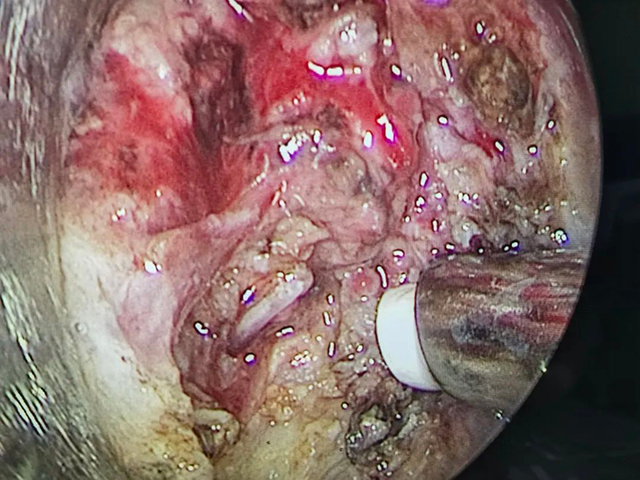

经过科内讨论,认为颈外切开创伤大,会造成更大的二次伤害,决定先采取喉镜下下咽异物探查取出术,若无法找到异物,再采取颈外切开手术。

准备就绪后,王剑顺利在喉镜下为刘大爷取出异物,术后咽喉部疼痛明显缓解。